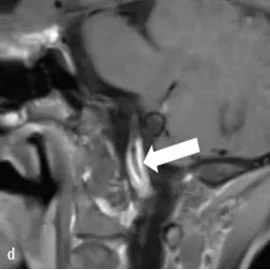

Intraorbital Findings in Giant Cell Arteritis on Black Blood MRI (Nov 2022)

This multicenter study examines orbital MRI findings using black blood (vessel wall) MRI in patients with Giant Cell Arteritis. Figure shows enhancement of the ophthalmic artery using VW-MRI (arrows).

Ophthalmic Artery Vessel Wall Inflammation in a Patient With Giant Cell Arteritis Presenting With Vision Loss (Mar 2024)

We report scalp and orbital MR findings in a patient with giant cell arteritis with inflammation of the temporal and ophthalmic arteries.

Orbital magnetic resonance imaging of giant cell arteritis with ocular manifestations: a systematic review and individual participant data meta-analysis (May 2023)

We systematically review all orbital MRI findings of patients with biopsy-proven GCA and visual disturbances. We report the clinical/exam findings and prevalence of orbital imaging findings in this disease.